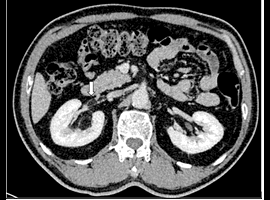

Citation: KO Cheung, CY Cheung, SW Sim, et al. Aggressive Renal Angiomyolipoma with Renal Vein Thrombosis: A Rare Complication. Clin Image Case Rep J. 2021; 3(10): 194.